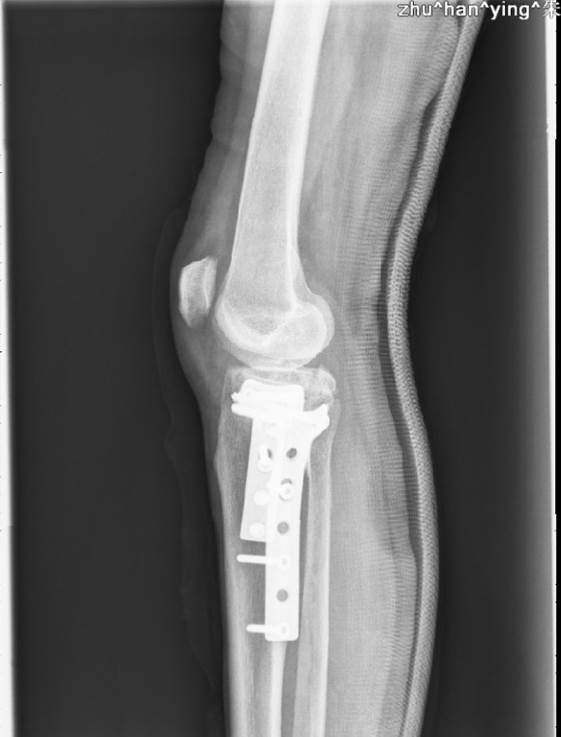

右侧胫骨平台骨折切开复位钢板内固定术 病例中心 诊疗助手 爱爱医医学网

右胫骨平台及胫骨上段骨折内固定术后 磐安骨伤医院

右侧胫骨平台骨折内固定术后 病例中心 诊疗助手 爱爱医医学网

一例右侧胫骨平台骨折患者的内固定手术治疗分享 病例中心 诊疗助手 爱爱医医学网